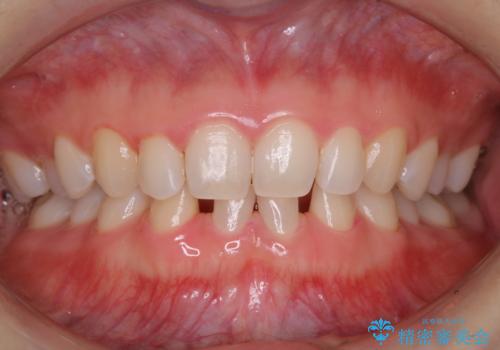

- すき間の部分の歯磨きがしずらく、クリーニング希望で来院されました。今後はセラミックによる治療を考えてとの事でした。PMTC(保険外治療)30分コースを行いました。

PMTC(保険外治療)とは、歯垢・歯石・着色などを除去することです。磨きのこしなどにより歯垢が付着し続けると、歯石に変化していきます。歯石になってしまったら、歯ブラシだけで落とすことができなくなります。そのため歯科医院での専門的な機械・材料を使用してのクリーニングが必要です。